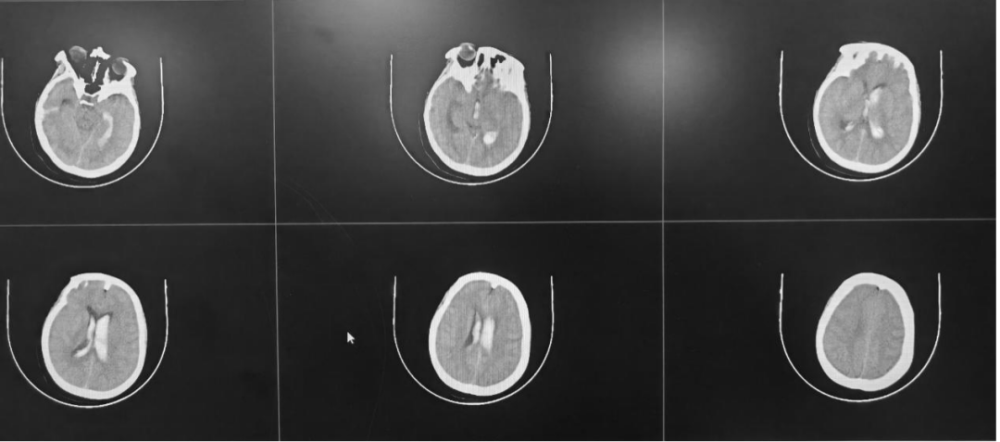

术前CT

王女士2年前因癫痫发作,在外院检查发现颅内存在较大畸形血管团,供血及引流血管情况复杂,因惧怕手术风险,一直未接受手术治疗。4天前,王女士突发头痛,伴有频繁恶心呕吐,无法行走,意识反应逐渐下降,随后被紧急送至我院急诊医学科。经头颅CT检查,提示脑室出血、脑肿胀、左侧颞叶稍高密度影、点状钙化灶。面对患者脑室出血、畸形血管团较大等复杂状况,手术难度极大,风险高,术中脑血管畸形破裂出血的可能性大,甚至可能危及生命。神经外科二病区纪文军主任医师团队开展深入讨论,制定了详尽的手术方案,最终与患者及家属充分沟通后决定为其行介入栓塞术。